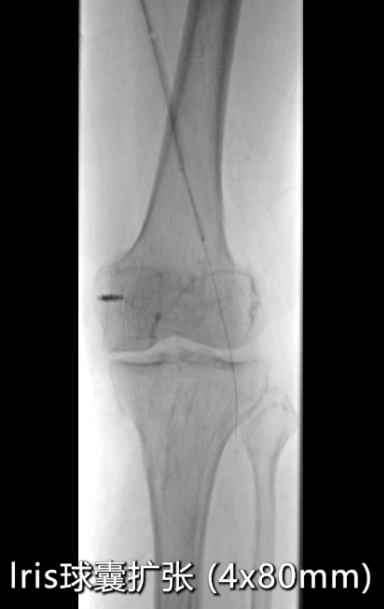

药物球囊扩张后造影显示:支架远端(临近P2段)存在局部狭窄,使用5×150mmIris球囊对病变段再次预扩;

扩张后出现小夹层,血流速度仍较慢,采用4×80mmIris球囊对病变段再次预扩